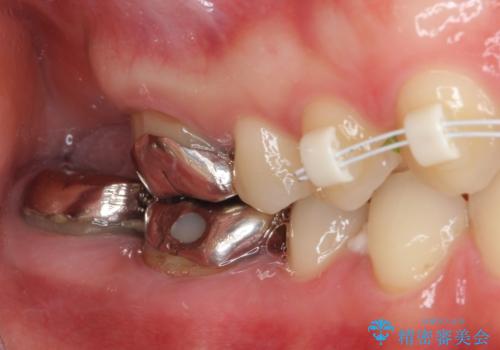

- 前歯の隙間と奥歯の目立つ銀歯を気にして来院された患者様です。

インビザラインにより下顎前歯の隙間を閉じるとともに、奥歯の咬み合わせを改善させることとしました。

矯正治療後には、銀歯のクラウンをセラミッククラウンへ替える補綴治療を行うこととしました。